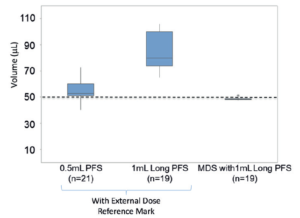

Figure 3: Ophthalmologists attempted to deliver a 50 μL dose using the MDS and conventional prefilled syringes.

GS In addition to development sponsor and device developer, there was buy-in from primary container component suppliers, CMOs and filling equipment manufacturers. It was a situation where there was a convergence and alignment of interests. Several syringe suppliers, who may have been left out of the microlitre dosing space, looked at the MDS as an enabling technology. A syringe that typically delivers millilitre doses can now deliver accurately and precisely a microlitre dose. Figure 3 shows results from a study in which ophthalmologists attempted to deliver a 50 μL dose using the MDS and conventional prefilled syringes, and which demonstrates how effective the MDS is in improving dosing accuracy. In addition, the Santen team delegated a lot of decision making to Congruence, which was very important to move the device development fast. The Santen team’s integrated approach included involvement in all aspects of drug fill-finish tasks even if it did not involve a device component. This ensured that decisions in the drug fill-finish process did not blindside the device development team.